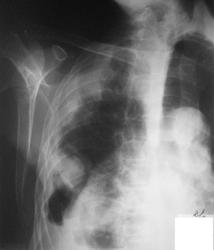

3. правый бок

а на боковой если посмотреть в переднем отделе огк, это что за полость. а так тоже за зло, с метестазами

Мне тоже не ясно это за полость, вопрос с образованием решен, но что за уровни жидкости?